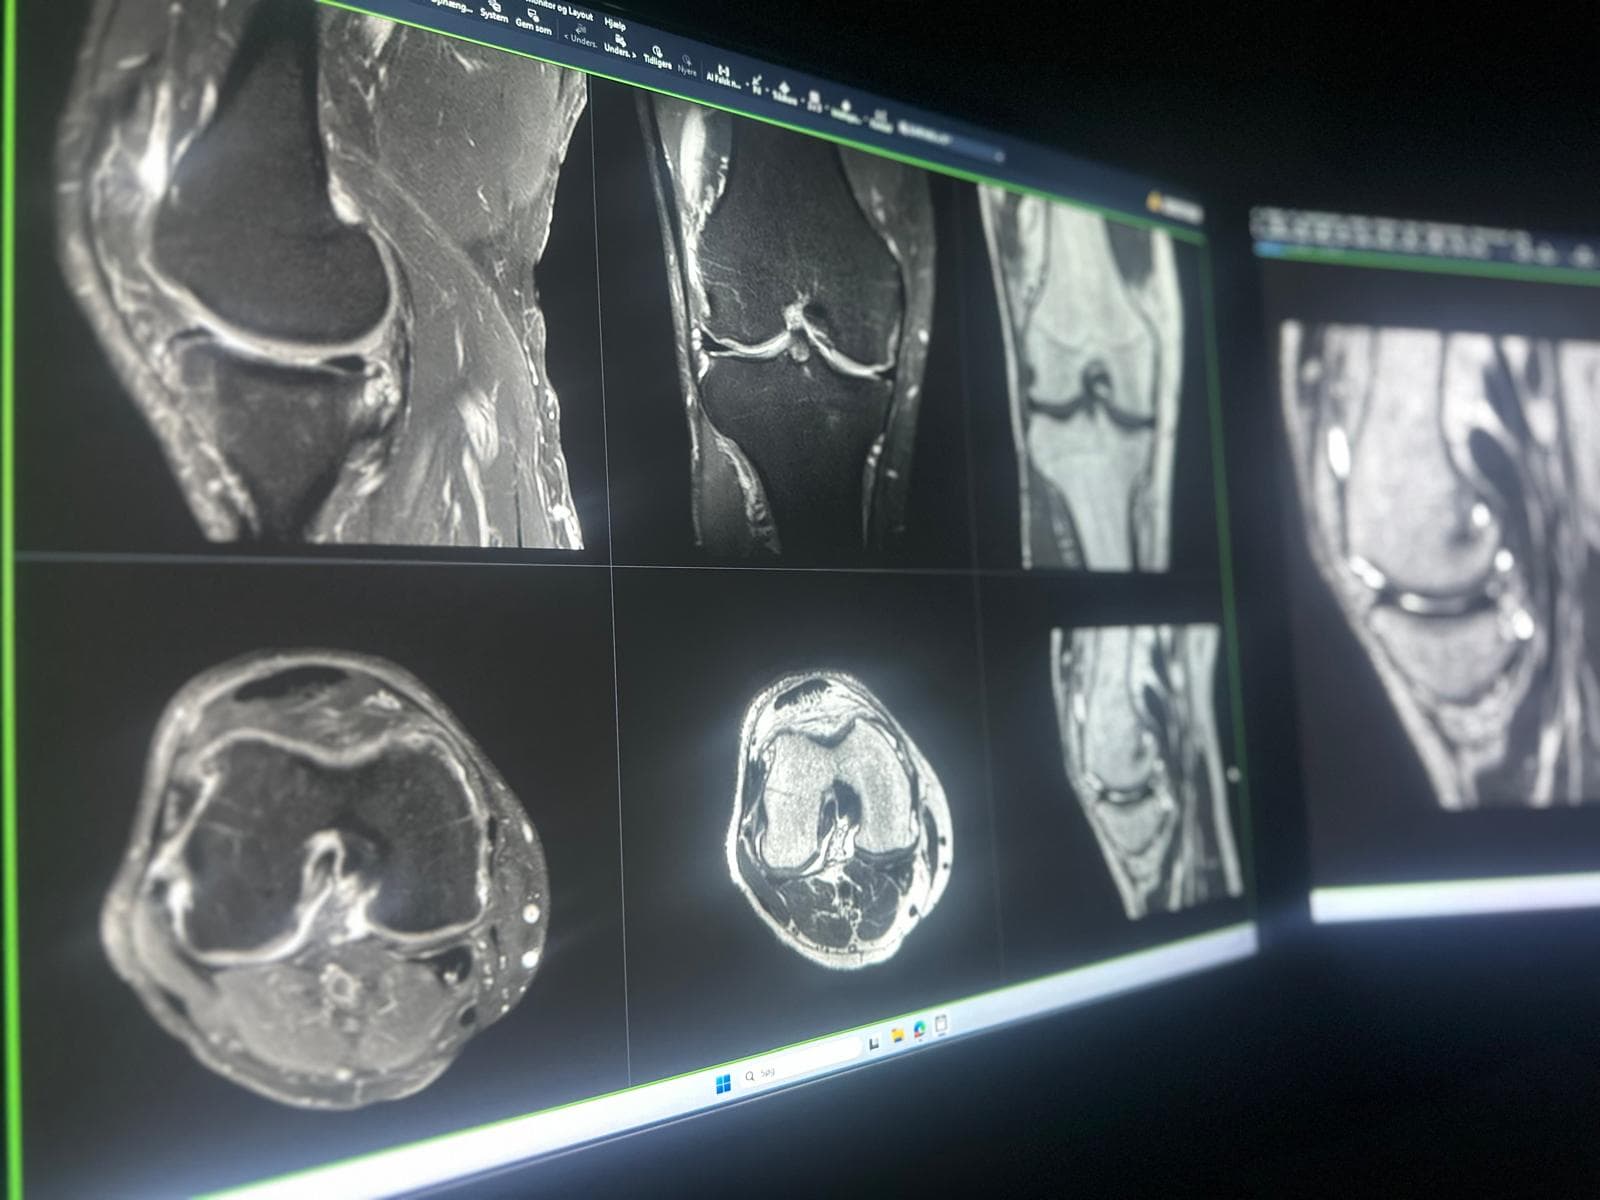

Eksempler fra reelle MSK-kontekster, herunder skulder, knæ, ankel og håndled, hvor strukturerede second opinions ofte giver størst klinisk værdi.

Komplekse skader, smerter, instabilitet, sene/ligament‑patologi, marvabnormiteter og postoperative tilfælde.